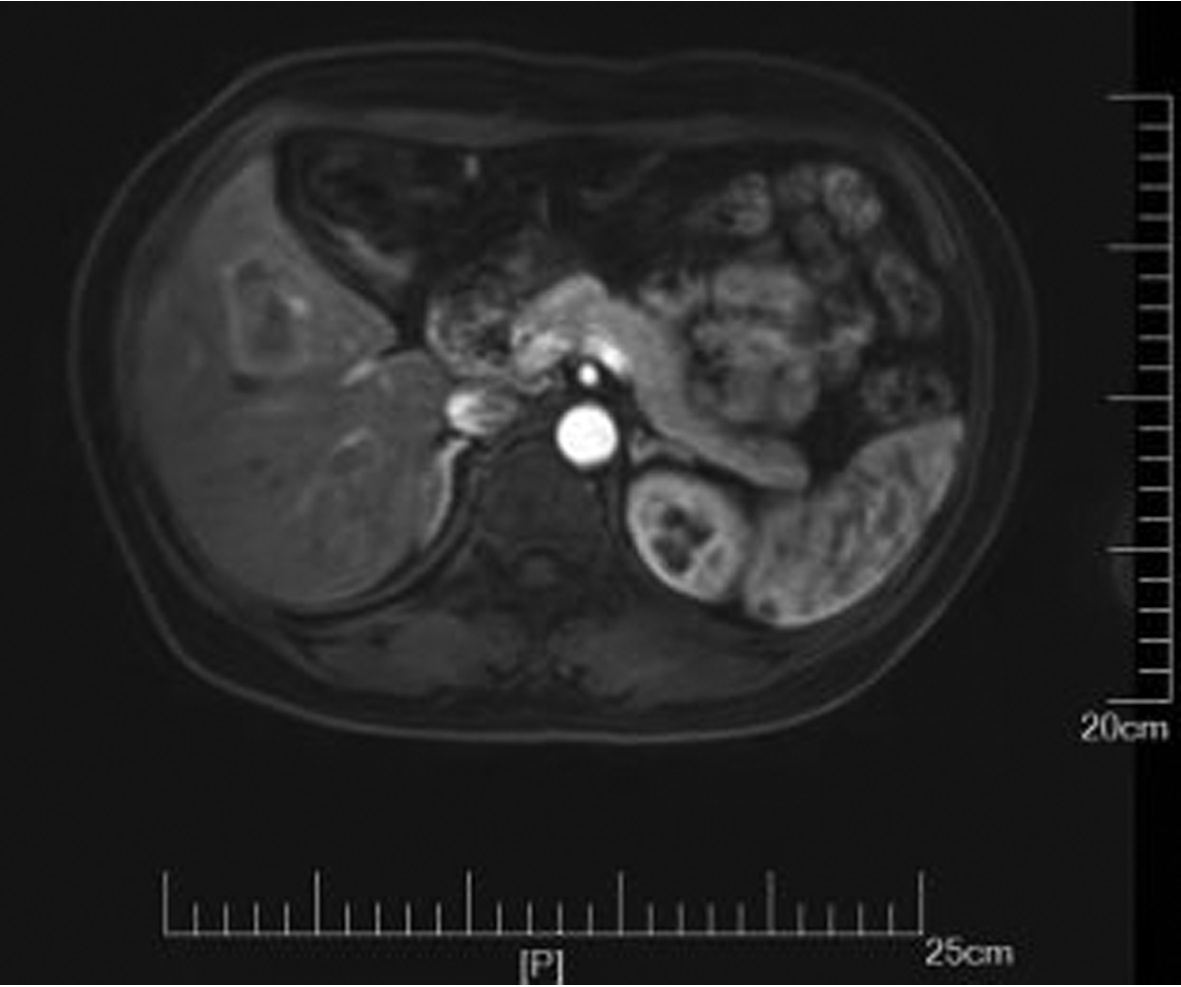

IgG4-related retroperitoneal fibrosis: A case report

Zhaoxia LI, Yang LIU, Nan LI, Zhuhui JI, Guijie XIN

2022, 38(5): 1126-1128. DOI: 10.3969/j.issn.1001-5256.2022.05.030

Abstract(758) HTML (364) PDF (2161KB)(55)

Abstract: